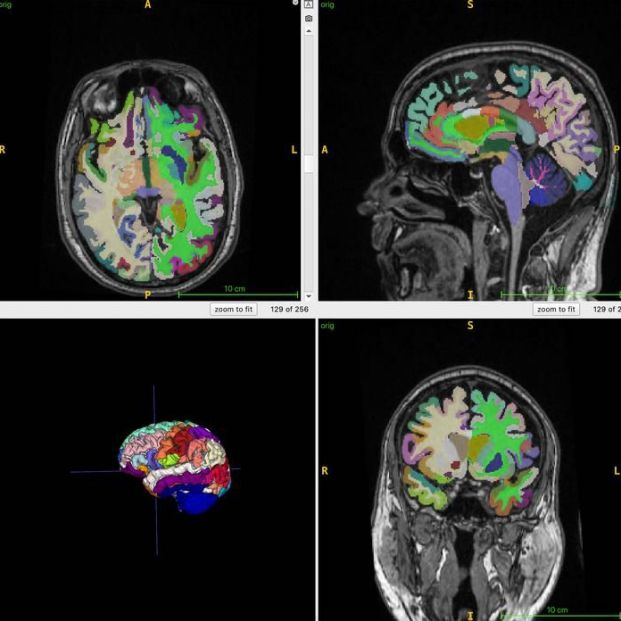

Imágenes cerebrales del estudio. (Cyrus Raji y RSNA)

La edad cerebral es la estimación computacional de la edad cronológica a partir de una resonancia magnética estructural del cerebro . La masa muscular, medida mediante resonacia magnética corporal, puede ser un marcador indirecto para diversas intervenciones destinadas a reducir la fragilidad y mejorar la salud cerebral. Asimismo, la edad cerebral predicha por imágenes cerebrales estructurales puede brindar información sobre los factores de riesgo de la enfermedad de Alzheimer, como la pérdida muscular.

Para el estudio en curso, se examinó mediante resonancia magnética corporal completa a 1.164 personas sanas (52% mujeres) de cuatro centros. La edad cronológica media de los participantes fue de 55,17 años. Los investigadores combinaron la resonancia magnética con secuencias ponderadas en T1, una técnica que produce imágenes donde la grasa se ve brillante y el líquido se ve oscuro. Esto permite obtener imágenes óptimas del tejido muscular, adiposo y cerebral. Se utilizó un algoritmo de inteligencia artificial (IA) para cuantificar el volumen muscular total normalizado, la grasa visceral (grasa abdominal oculta), la grasa subcutánea (grasa subcutánea) y la edad cerebral.